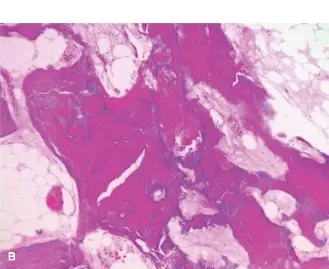

مرض باجيت العظمي (Paget's Disease of Bone) هو حالة مزمنة تؤثر على عملية إعادة تشكيل العظام الطبيعية في الجسم. عادةً، تقوم العظام القديمة بالتحلل ثم تُستبدل بعظام جديدة وصحية في عملية مستمرة تسمى إعادة التشكيل العظمي. في مرض باجيت، تصبح هذه العملية مضطربة وغير منظمة.

تبدأ المشكلة بزيادة مفرطة في نشاط خلايا هدم العظم (الخلايا الآكلة للعظم)، مما يؤدي إلى تكسير العظم القديم بسرعة كبيرة. في محاولة لتعويض هذا الفقدان، تزيد خلايا بناء العظم (الخلايا البانية للعظم) من نشاطها لإنتاج عظم جديد. ومع ذلك، فإن العظم الجديد الذي يتكون يكون غير منظم، ضعيفًا، وهشًا، وغالبًا ما يكون أكبر حجمًا من العظم الطبيعي. يُوصف هذا العظم الجديد بأنه "عظم منسوج" بدلاً من "عظم صفائحي" منظم.

• الأهم من ذلك، أنها تكشف عن السمات الكلاسيكية لمرض باجيت في عظم الفخذ المصاب:

• تثخن القشرة العظمية: سماكة غير طبيعية في الطبقة الخارجية للعظم (القشرة)، خاصة على الجانبين الداخلي والخارجي.

• خشونة الترابيق العظمية: نمط غير منظم وسميك للشبكة الداخلية للعظم، غالبًا ما يوصف بمظهر "الصوف القطني" أو "العظم المنسوج".

• تضخم العظم: زيادة في القطر الكلي لجسم عظم الفخذ مقارنة بالعظم الطبيعي.

• تقوس العظم: قد يظهر تقوس طفيف للأمام في جسم عظم الفخذ، وهو تشوه شائع في العظام الطويلة المصابة بباجيت.

• يُظهر خط الكسر نفسه أنه يمر عبر هذا الهيكل العظمي المتغير بشكل كبير، مما يؤكد أنه كسر مرضي في سياق مرض باجيت.

صورة أشعة سينية أمامية خلفية أولية تُظهر كسرًا تحت المدور في عظم مصاب بمرض باجيت. لاحظ التثخن الواضح في القشرة العظمية، وخشونة الترابيق، والتضخم العام في الجزء العلوي من الفخذ، وهي سمات مميزة لمرض باجيت.